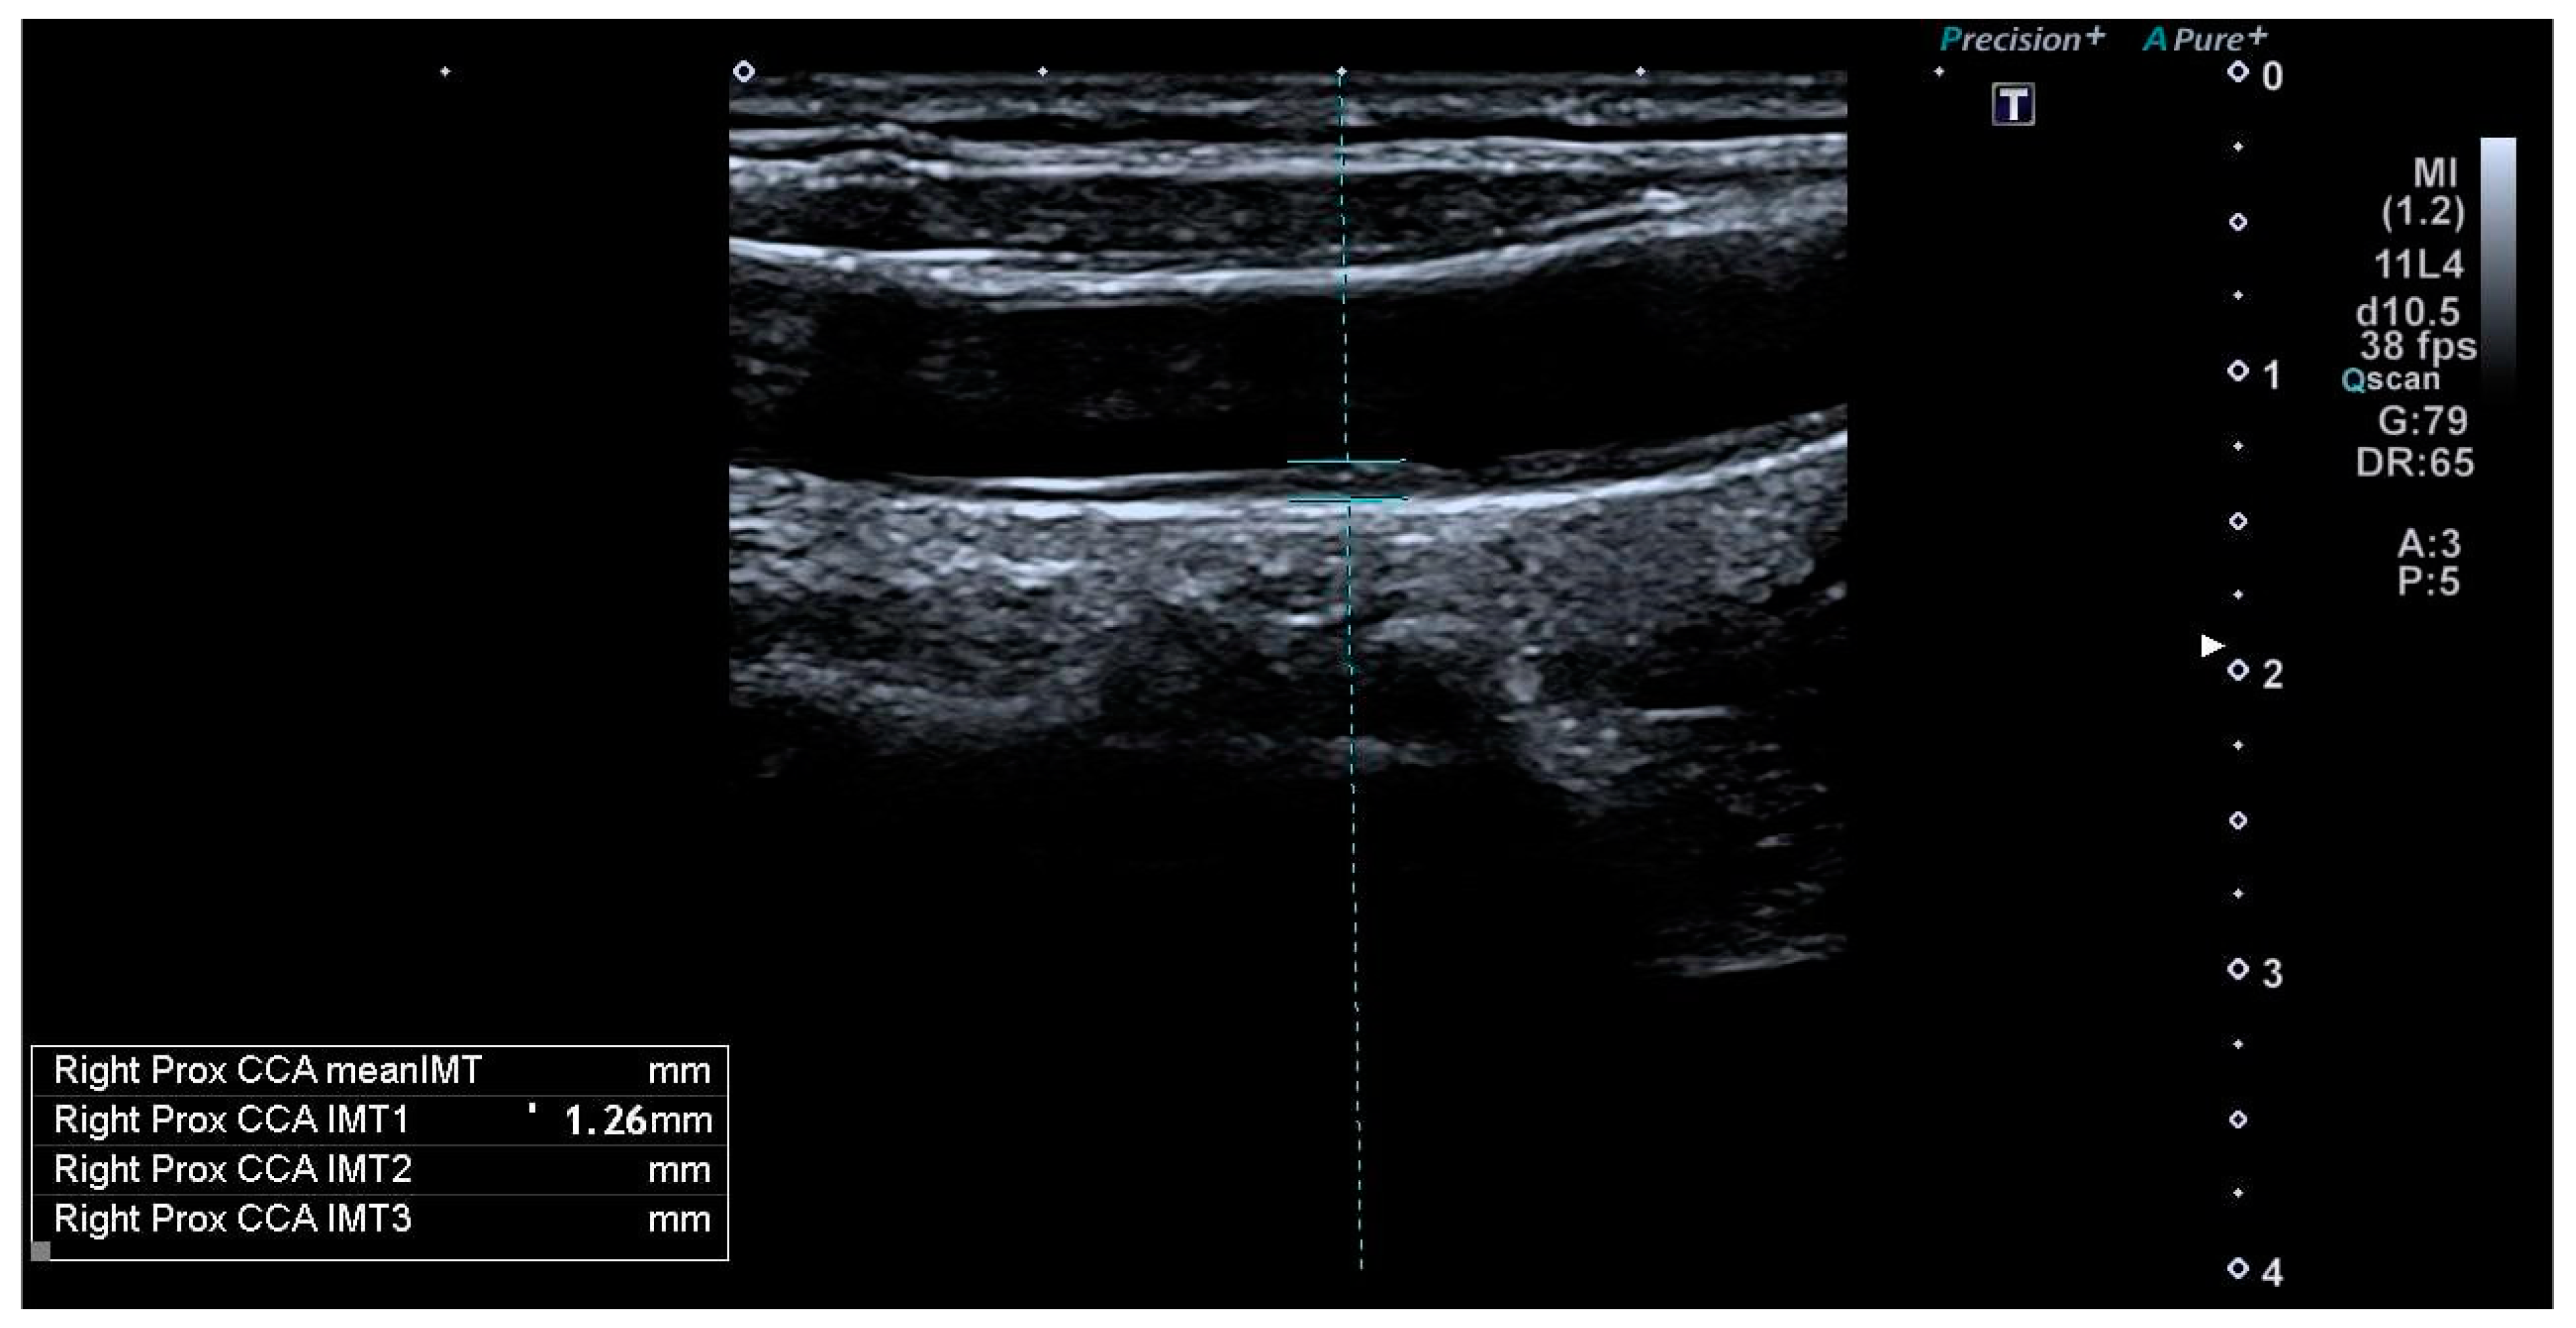

| Internal-CIMT (mm) | 0.7 ± 0.13 | 0.59 ± 0.15 | 0.021 * |

| Common-CIMT (mm) | 0.65 ± 0.15 | 0.56 ± 0.11 | 0.002 * |

| Higher-than-normal (>75th percentile **) Common-CIMT values (n/%) | 28/44, %64 | 7/44, %16 | 0.003 * |